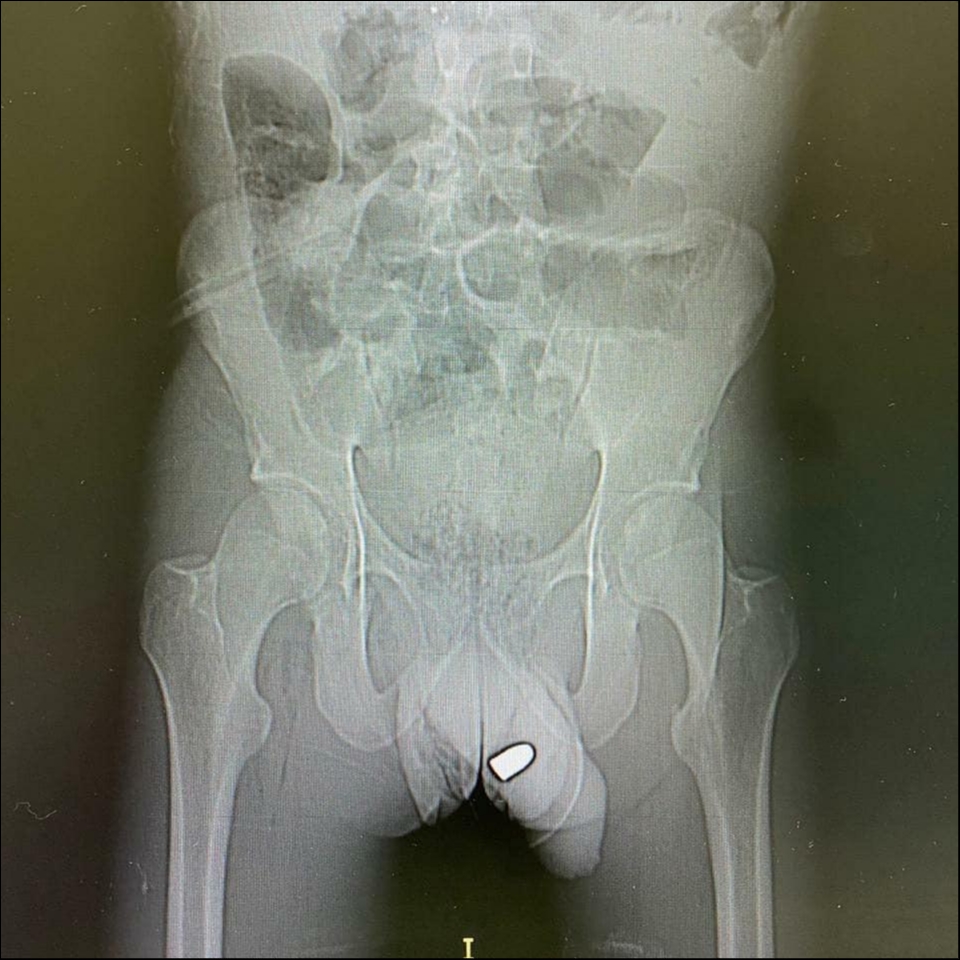

1. PHOTO-2020-08-05-07-16-33 2.jpg

PHOTO-2020-08-05-07-16-33.jpg